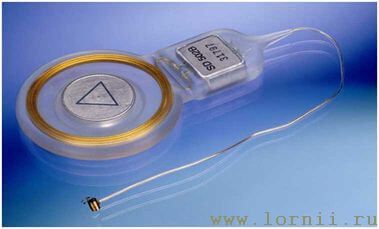

Функция системы Vibrant Sоundbridge заключается в трансформации звуков непосредственно в колебания цепи слуховых косточек среднего уха или в колебания жидкости улитки (перилимфы). Система состоит из двух частей: внутренней – имплантируемой, импланта (Vibration Ossicular Prosthesis, VORP) и наружной – аудиопроцессора (Audio Processor, AP).

Имплантируемая внутренняя часть состоит из постоянного магнита, катушки, принимающей электромагнитные сигналы, соединительного кабеля и устройства, приводящего в движение слуховые косточки или жидкость улитки – Floating Mass Transducer (FMT).

Аудиопроцессор содержит микрофон, элемент питания и электронику. Он располагается снаружи, скрыт волосами и удерживается с помощью магнита (рис. 4, 5).